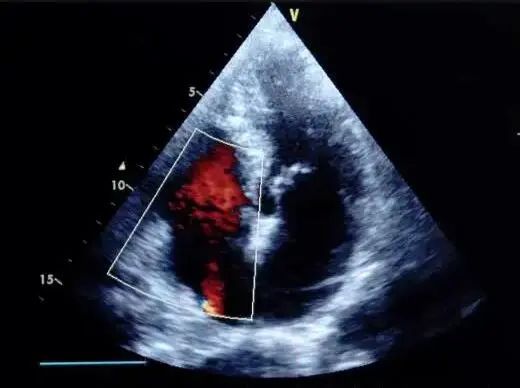

定期筛查及时诊断

建议肺动脉高压高危人群每年进行一次肺动脉高压筛查,通过超声心动图可以较准确地估计肺动脉收缩压。如筛查结果有异常或出现症状,医生会要求患者行右心导管检查,这是确诊肺动脉高压的金标准,肺动脉高压确诊:也是进行鉴别诊断、评估病情和治疗效果的重要手段。